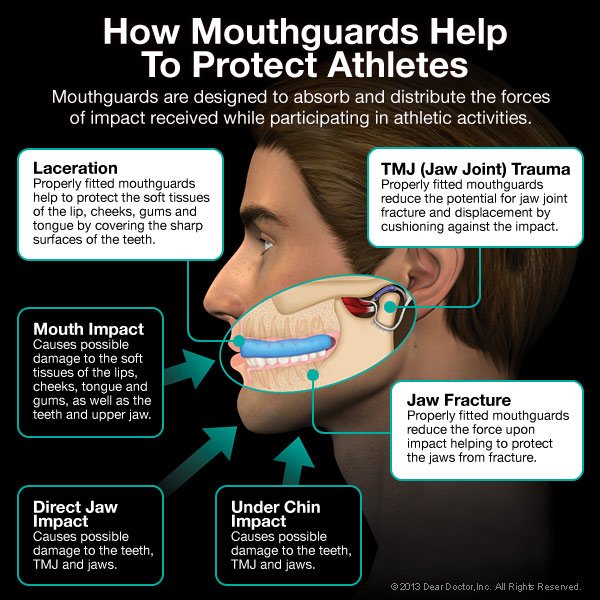

What’s the best treatment for facial trauma? Prevention. Always wearing seat belts, using proper helmets and protective gear when playing sports, and staying out of dangerous situations (like driving while impaired, tired or distracted) can go a long way toward keeping you safe. If you’re engaging in athletic activities that carry any risk of facial injury, wear a properly fitted mouthguard — this small piece of protective equipment can save you a lot of potential harm.